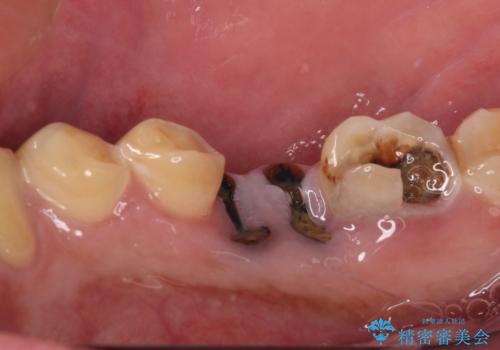

- 奥歯が痛く、放置した虫歯があるとのことで来院された患者様です。

全体的に汚れが多く、歯の表面の脱灰が全体的に認められましたが、まずは奥歯の虫歯治療から行うこととしました。

根っこだけとなっている歯は抜歯をし、奥の大きな虫歯となっている歯は、神経を取り除く可能性を考慮しながら処置を進めて行くこととしました。